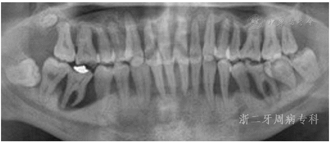

口腔卫生欠佳,软垢指数:2;牙石指数:3;全口牙龈充血红肿;平均牙周探诊深度(PD)7.0 mm,PD≥7 mm的位点占所有检查位点的63.3%(114/180),其中17颊侧远中、17舌侧远中、34舌侧远中、36颊侧近中、46舌侧近中PD深达12 mm;平均附着丧失(CAL)9.3 mm、CAL≥5 mm的位点数为98.3%(177/180);BOP(+)%:100%;37、46松动度Ⅲ度,11~17、21、22、24~27、32、34、41~43、45、47松动Ⅱ~Ⅲ度,余牙松动度Ⅰ度;36、46Ⅲ度根分叉病变。16、26、36、46牙釉质发育不Ⅲ全,11扭转,37缺失舌向倾斜,12、14~16、24、25、41、42咬合时出现异常动度,31、41可见1.5 mm左右牙间隙(图1,图2)。牙髓活力测定:17、34牙髓活力正常,36、37、46"40"无反应。

全口曲面体层X片示:全口牙槽骨广泛性水平吸收,46牙槽骨吸收超过根尖;36根尖周和根分叉区低密度影;13、22、23、33~35、43~45、47牙槽骨吸收达根长1/2~2/3,余牙牙槽骨吸收至近根尖(图3)。